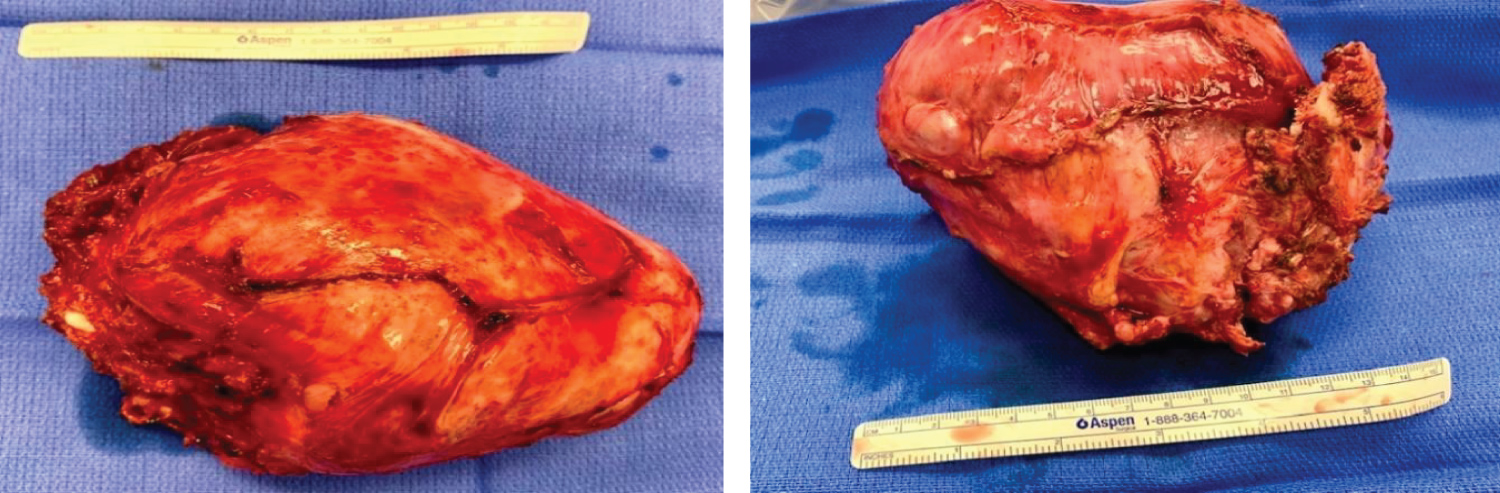

A 33-year-old man presented with right chest and arm pain, right arm sensory and motor deficits along with the ulnar nerve distribution, and right arm anhidrosis. Imaging was remarkable for a 13.4 cm × 12.3 cm heterogeneously enhancing mass from the right 2nd rib growing into the right thoracic inlet and right lung apex. The tumor caused normal lung parenchymal deviation with extensive right-sided neoplastic neuroforaminal involvement and brachial plexus compression (Figure 1). A biopsy of the mass was reported as mesenchymal chondrosarcoma. After chemotherapy and radiation therapy, some of his symptoms, including right arm pain improved and the total tumor volume was slightly reduced. The patient was not taking pain medication at the time he was referred to our hospital for neuro/thoracic surgical consultations for possible tumor resection.

Figure 1: Preoperative Chest MRI image: Heterogeneously enhancing mass (arrows) in the right thoracic inlets and lung apex (13.4 cm × 12.3 cm).